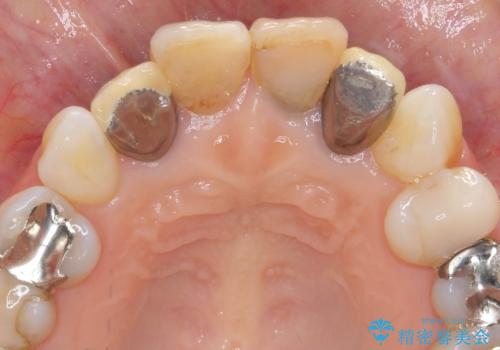

- 「黒ずんで、見栄えの悪い前歯をきれいにしたい。」と、前歯のセラミック治療を希望され来院されました。

全て根管治療のすでになされている歯の変色で、オールセラミッククラウンによる審美性の改善を計画します。

- 52.8万円(ジルコニアクラウン×4・仮歯×4)費用は治療当時の料金となります